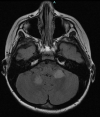

Viral infections can serve as a trigger for variable autoimmune, antibody-mediated demyelinating disorders. There is accumulating evidence that the severe acute respiratory syndrome coronavirus 2 (SARS-CoV-2) virus, causing coronavirus disease 2019 (COVID-19) infection and responsible for the current worldwide pandemic, can lead to a cascade of immune-mediated brain and spinal cord demyelinating injuries. However, such observation in the pediatric age group was only reported in very few patients. Thus, the heterogeneous spectrum of this phenomenon in children is still unfolding. We are reporting a case series of five pediatric patients with a variety of acute central nervous system (CNS) demyelinating disorders in the context of acute or recent COVID-19 infection. A 16-year-old female with anti-myelin oligodendrocyte glycoprotein (MOG) disorder, an eight-year-old male with acute disseminated encephalomyelitis (ADEM), a 13-year-old female with neuromyelitis optica spectrum disorder (NMOSD), and two 14 and 13-year-old females with new-onset multiple sclerosis (MS) are reported, all of whom presented acutely following COVID-19 infection. We propose that para and post-infectious CNS demyelinating disorders can potentially follow acute COVID-19 infection in children. Considering SARS-CoV-2 testing as a part of diagnostic workup is possibly useful. Awareness of the presence of this phenomenon can help in the recognition and management of those patients.